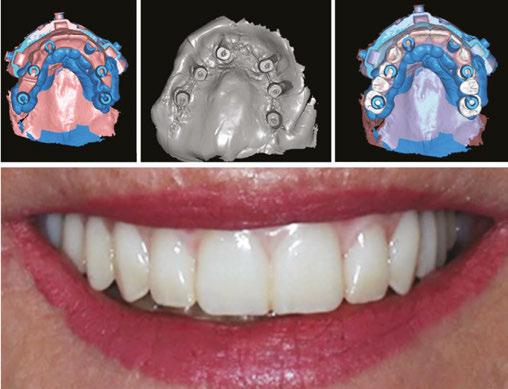

Grammetry is a method developed that rivals photogrammetry and analog implant impression techniques. Grammetry is the process of capturing a continuous arch scan with an intraoral scanner and a unique ScanBase tracking mechanism, preventing loss of accuracy ensuring scan quality. Utilizing a special Scanbase system, the scan bodies are connected together allowing for a continuous scan with the intraoral scanner, decreasing the chance of stitching errors. Described below are two Scanbase tracking systems that are utilized by the author in private practice. Both techniques provide simplified scanning, improved accuracy, and a fully digital workflow for full-arch implant cases.

When imported into a design software (e.g., Exocad), the OPTISPLINT scan will produce a digital file of implant positioning. Additional records include facial records, soft tissue records, and tooth/occlusal records (Figure 6).

After all the records are acquired, the scans may then be aligned and the patient’s implant prosthesis can be designed and fabricated (Figures 7A-7F). The OPTISPLINT technique enables clinicians to utilize a fully-digital workflow for a fraction of the cost of other digital methods. Patient factors are able to be eliminated as the OPTISPLINT can be scanned extraorally with the added benefit of acting as a verification jig prior to prosthetic delivery.

Figures 7A-7F: 7A. Alignment of facial record to teeth, to aid in smile design and tooth setup. 7B. Detecting implant position via scan region of OPTISPLINT jig. 7C. Alignment of patient’s teeth to soft tissue, to allow tooth setup at correct vertical dimension. 7D. Alignment of implant position to soft tissue. 7E. Digital design of patient’s prosthesis. 7F. Final prosthetic delivery

All of the digital files are then exported to the dental lab for fabrication of the full-arch implant prosthesis, utilizing a fully digital workflow (Figures 11A-11D). ScanLink and ScanBase

Figures 11A-11D: 11A. Intraoral scan of scan bodies with ScanLink and ScanBase. 11B. Soft tissue record. 11C. Alignment of all data including patient’s tooth positioning, occlusion at correct vertical dimension. 11D. Delivery of immediate fixed prosthesis

Summary

While intraoral scanning offers many advantages, such as patient comfort and digital integration, it faces significant challenges when utilized in full-arch implant impressions. The large surface area in edentulous cases, lack of stable reference points, lack of teeth or keratinized mucosa, and the similarities in scan body morphology make it difficult to distinguish and stitch together multiple images accurately. Innovative scanning techniques and scan body systems have strived to overcome these challenges. Grammetry, through utilization of a scan base system, allows the intraoral scanner to continuously capture data which has led to improved accuracy in full-arch digital implant impressions. OPTISPLINT and the CONnX Scan system are two types of these scan base systems that connect the scan bodies together, thus limiting stitching difficulties. With these techniques, the everyday clinician is able to utilize their intraoral scanner for a fully digital All-on-X workflow.